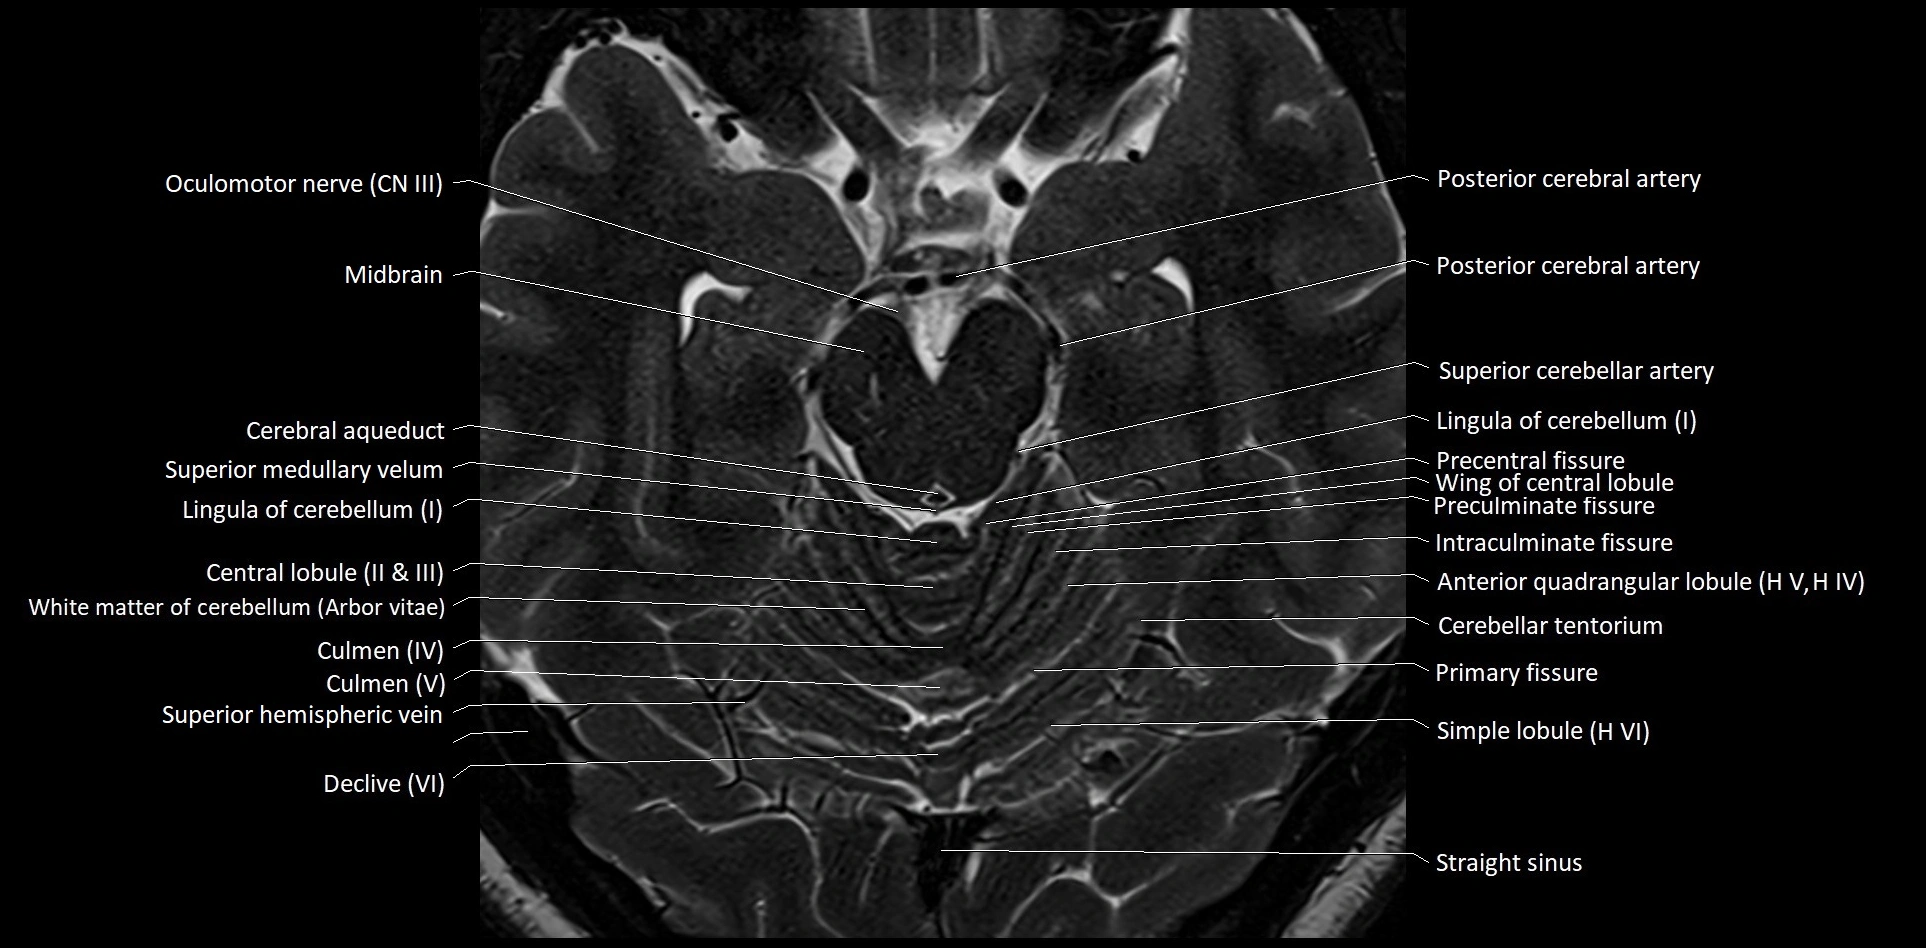

MRI images